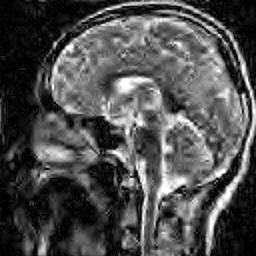

Hence both and should recover equally well. In the top row of Figure 1 we present the result of the flip test for a Gaussian random matrix. As is evident, the reconstructions and are comparable, thus indicating the RIP.

Having considered type II problems, let us now examine the flip test for a type I problem. As discussed, in applications such as MRI, X-ray CT, radio interferometry, etc, the matrix is imposed by the physical sensing device and arises from subsampling the rows of the DFT matrix .111In actual fact, the sensing device takes measurements of the continuous Fourier transform of a function . As discussed in BAACHGSCS ; BAGSAIEP , modelling continuous Fourier measurements as discrete Fourier measurements can lead to inferior reconstructions, and worse, inverse crimes. To avoid this, one must consider an infinite-dimensional compressed sensing approach, as in (2). See AHPRBreaking ; BAGSAIEP for details, as well as PruessmannUnserMRIFast for implementation in MRI. However, for simplicity, we shall continue to work with the finite-dimensional model in the remainder of this paper. Whilst one often has some freedom to choose which rows to sample (corresponding to selecting particular frequencies at which to take measurements), one cannot change the matrix .

It is well known that in order to ensure a good reconstruction, one cannot subsample the DFT uniformly at random (recall that the sparsifying transform is a wavelet basis), but rather one must sample randomly according to an appropriate nonuniform density AHPRBreaking ; Candes_Romberg ; Lustig ; WangAcre . See the bottom left panel of Figure 1 for an example of a typical density. As can be seen in the next panel, by doing so one achieves a great recovery. However, the result of the flip test in the bottom right panel clearly demonstrates that the matrix does not satisfy an RIP. In particular, the ordering of the wavelet coefficients plays a crucial role in the reconstruction quality. To explain this, and in particular, the high-quality reconstruction seen in the unflipped case, one evidently requires a new analytical framework.

Note that the flip test in Figure 1 also highlights another important phenomenon: namely, the effectiveness of the subsampling strategy depends on the sparsity structure of the image. In particular, two images with the same total sparsity (the original and the flipped ) result in wildly different errors when the same sampling pattern is used. Thus we conclude that there is no one optimal sampling strategy for all sparse vectors of wavelet coefficients.

The estimate (12) both agrees with the conclusion of the flip test in Figure 1 and explains the results seen. Flipping the wavelet coefficients changes the local sparsities . Therefore to recover the flipped image to the same accuracy as the unflipped image, (12) asserts that one must change the local numbers of measurements . But in Figure 1 the same sampling pattern was used in both cases, thereby leading to the worse reconstruction in the flipped case. Note that (12) also highlights why the optimal sampling pattern must depend on the image, and specifically, the local sparsities. In particular, there can be no optimal sampling strategy for all images.